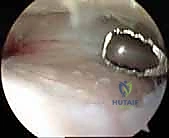

الخطوة الثالثة: التنظيف وإزالة الغضاريف (Debridement)

باستخدام أدوات متخصصة (مثل Shaver و Curette)، يتم تنظيف المفصل من أي نتوءات عظمية (Osteophytes) والأنسجة الملتهبة. بعد ذلك، يتم كشط وإزالة ما تبقى من الغضروف التالف من على أسطح عظمة الظنبوب وعظمة الكعب وصولاً إلى العظم الإسفنجي السليم النازف (Bleeding Subchondral Bone). هذه الخطوة حاسمة جداً، فالعظم النازف هو الذي سيحفز عملية الشفاء وتكوين عظم جديد للدمج.

الخطوة الرابعة: التحضير البيولوجي للأسطح العظمية

لضمان أقصى درجات الاندماج، قد يقوم الجراح بعمل ثقوب دقيقة في العظم (Microfracture) لزيادة تدفق الخلايا الجذعية وعوامل النمو من نخاع العظم إلى منطقة الدمج.